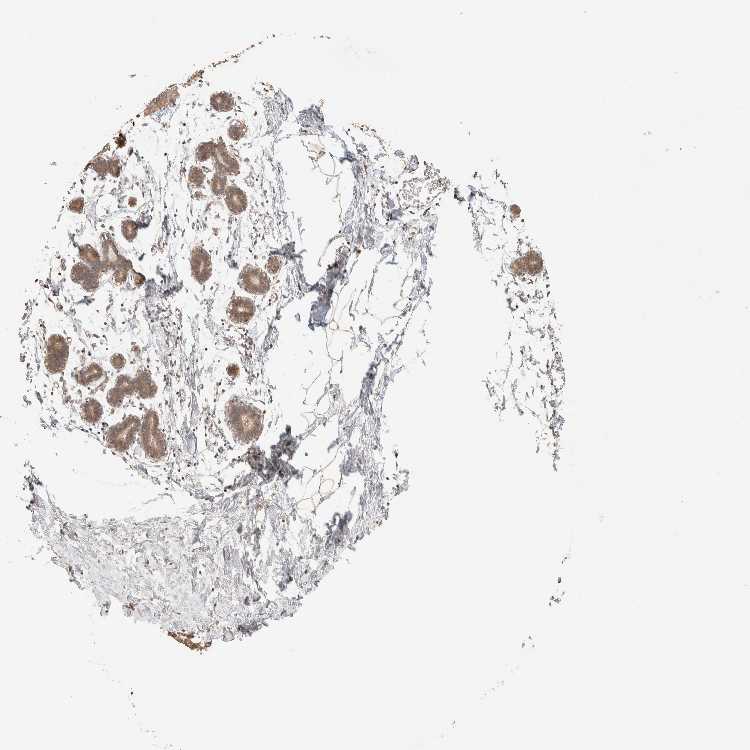

BREAST - Antibody stainingi

Antibody staining in the annotated cell types in the current human tissue is reported as not detected, low, medium, or high, based on conventional immunohistochemistry profiling in selected tissues. This score is based on the combination of the staining intensity and fraction of stained cells.

Each image is clickable and will lead to virtual microscopy that enables deeper exploration of all samples and also displays staining intensity scores, fraction scores and subcellular localization as well as patient and tissue information for each sample.

Antibody HPA022824

Adipocytes Low

Glandular cells Medium

Myoepithelial cells Medium